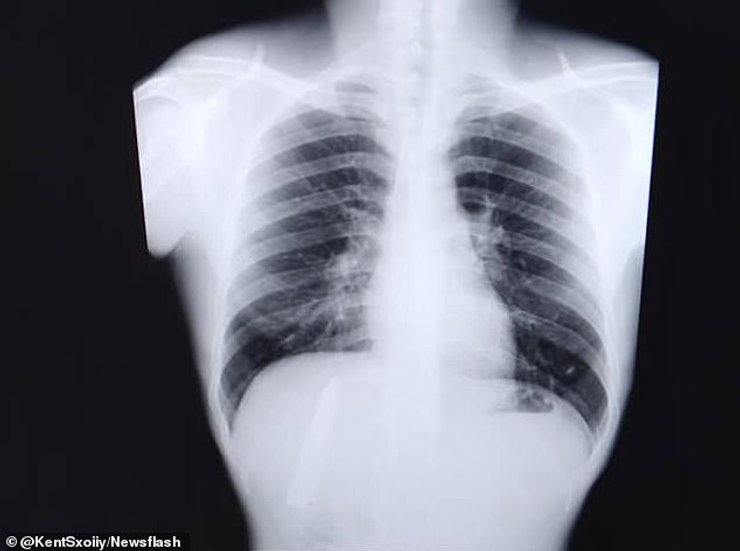

Кент Райан Томао и его рентгеновский снимок | Фото: The Guardian

Однако в марте 2021 года молодой человек захотел устроится на работу на шахту в провинции Агусан-дель-Сур. Ему пришлось пройти медицинское обследование сделать рентген. Каково же было его удивление, когда оказалось, что все это время он жил с лезвием в груди.

Видимо, когда его ударили ножом, лезвие отломалось и застряло в теле, чудом не задев сердце, или легкие.